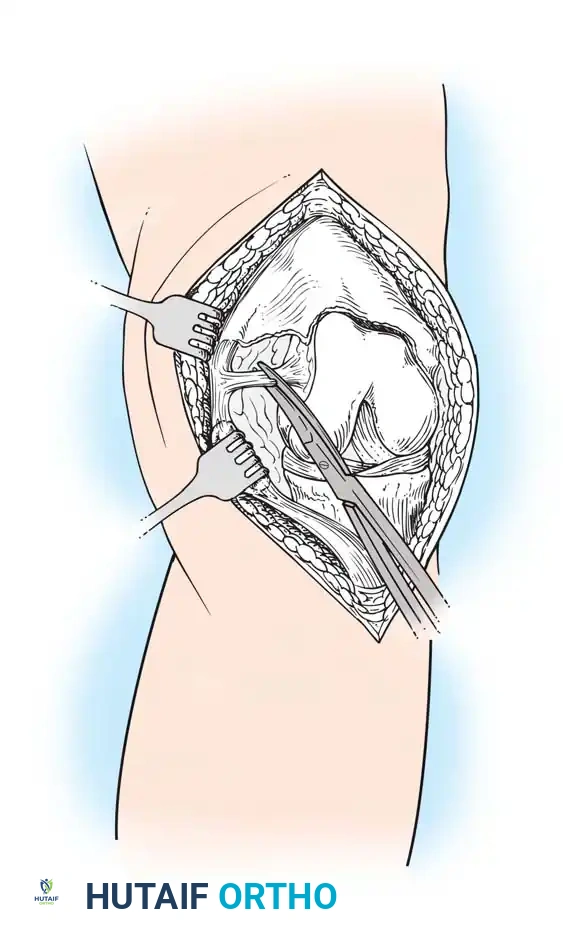

The Medial Parapatellar Retinacular Approach

The standard and most versatile retinacular incision in TKA is the medial parapatellar approach. It provides extensile exposure and is suitable for nearly all primary and revision scenarios.

- Make the skin incision with the knee in flexion. This allows the subcutaneous tissue to fall medially and laterally, naturally improving exposure.

- If a preexisting anterior scar is present in a usable position, incorporate it. If multiple previous incisions exist, choose the most lateral usable incision. The blood supply to the skin of the anterior knee predominantly arises from the medial side; violating this principle risks catastrophic skin necrosis.

- Ensure the skin incision is long enough to avoid excessive tension during retraction.

- Keep the medial skin flap as thick as possible by maintaining dissection just superficial to the extensor mechanism.

- Extend the retinacular incision proximally along the length of the quadriceps tendon, leaving a 3- to 4-mm cuff of tendon on the vastus medialis to facilitate robust closure.

- Continue the incision around the medial border of the patella, extending 3 to 4 cm onto the anteromedial surface of the tibia, parallel to the medial border of the patellar tendon.

- Expose the medial side of the knee by subperiosteally elevating the anteromedial capsule and the deep medial collateral ligament (MCL) off the tibia, extending to the posteromedial corner of the knee.

- Extend the knee and evert the patella. This allows for a routine release of the lateral patellofemoral plicae. In obese patients, if eversion is difficult, develop the lateral subcutaneous flap further so the patella can be everted underneath this tissue without avulsing the patellar tendon.

⚠️ Surgical Warning: Patellar Tendon Avulsion

During all maneuvers that place tension on the extensor mechanism—especially knee flexion and patellar retraction—pay careful attention to the patellar tendon attachment at the tibial tubercle. Avulsion of the patellar tendon is a devastating complication that is notoriously difficult to repair.